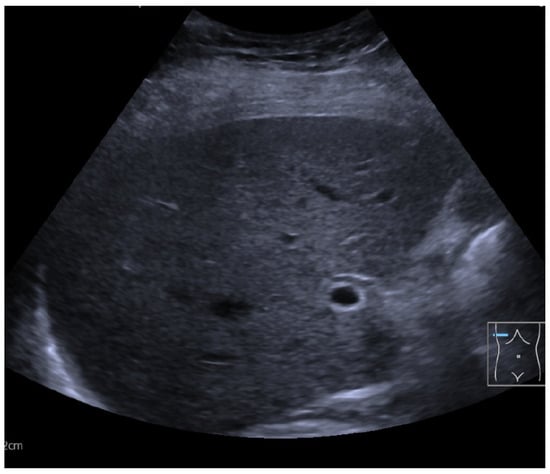

2. Case Presentation

Diagnostic Workup